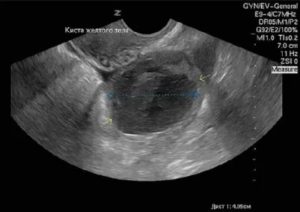

УЗИ снимок кисты желтого тела.

Уточнить диагноз позволяет УЗИ.

- УЗИ брюшной полости показывает объемные эхогенные новообразования и дает оценку их размерам. Во время беременности на УЗИ достаточно сложно определить желтое тело, из-за его небольшой величины;